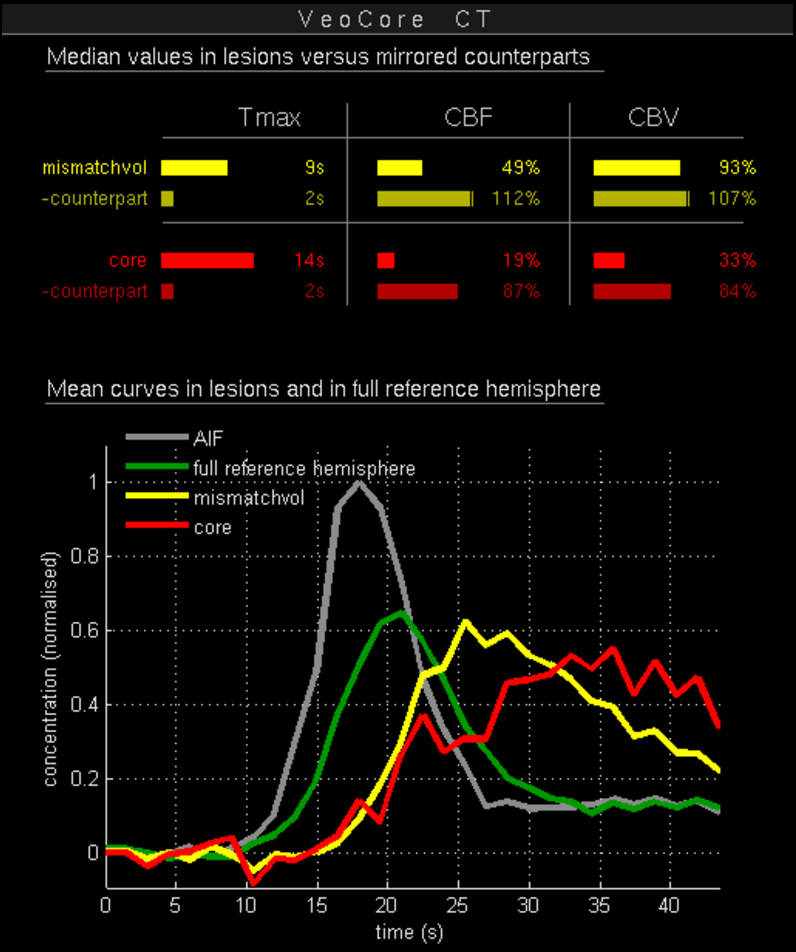

16.1. Overview

VEOcore is a fully automated image processing tool to calculate quantitative measures of affected brain tissue and healthy tissue. Therefore, this manual covers the instructions on how to interpret the results. It’s an extension the mRay Server application and the results can be viewed inside the mRay Client. Furthermore processed results can be automatically forwarded to the PACS.

16.2. Triggering the data processing

VEOcore does not have a user-interface. Data is processed fully automated on reception of DICOM series. All series should be sent in one rush, otherwise the data processing might be invoked multiple times, and result images might appear in the target PACS multiple times.

For MR and CT, the following DICOM images can be sent to the application. For details on series naming conventions as well as compatible and recommended measurement parameters such as slice thickness, repetition times etc. please refer to the Annex.

16.2.1. Computed Tomography (CT))

-

CT perfusion (VPCT)

Repeatedly acquired volumes of low-dose CTs acquired during injection of a contrast bolus. This series is often called VPCT (Volume-Perfusion-CT). -

Non-contrast native CT image (optional)

Native image before contrast injection with a reconstruction kernel optimised for brain tissue. Sending this image is optional, but recommended. If sent together with the VPCT, it is used as background for the overlay with the segmented core and mismatch volume.

16.2.2. Magnetic Resonance Imaging (MRI)

-

MR perfusion (DSC-Perfusion) (optional)

Repeatedly acquired volumes of echo-planar imaging acquired during injection of a contrast bolus. This measurement technique is often referred to as DSC-Perfusion (Dynamic-susceptibility-contrast perfusion). Sending a perfusion measurement is optional in MR. If not send, only the infarction core will be segmented based on the ADC (see below). -

MR ADC

Apparent-Diffusion-Coefficient (ADC), berechnet aus einer diffusions-gewichteten Sequenz (DWI-MR). Das senden des direkt am MR-Scanner berechneten ADC ist unbedingt notwendigan ADC, VEOcore berechent keinen ADC selbst aus den DWI-Daten. -

MR DWI (optional)